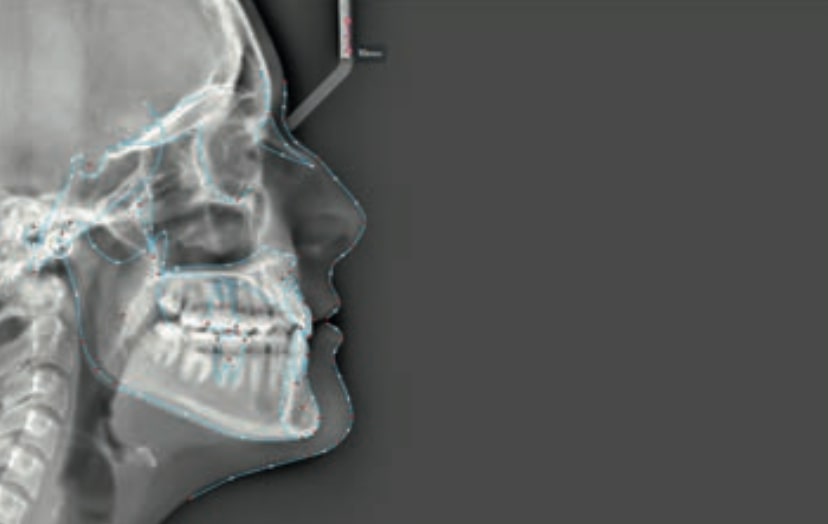

Chief complaint: The patient, a 19-year-old woman, was evaluated to undergo orthodontic treatment using the Angel Aligner Pro system. She presents with a skeletal Class III, mesofacial, with a dental Class III malocclusion and a 2 mm deviation of the lower midline to the left. Teeth 33 and 43 are out of the arch and cortical bone, with a crossbite issue on tooth 33. Fortunately, no functional issues affecting swallowing or breathing have been detected. The patient’s motivation for starting treatment was a general review of her dental and aesthetic health. The soft tissue analysis reveals mandibular protrusion that influences her facial profile. This diagnosis highlights the need for a comprehensive approach to address dental and skeletal misalignments, improving both the patient’s functionality and facial aesthetics.

- Skeletal class III

- Soft Tissue Analysis: Jaw protrusion

Clinical examination and diagnosis